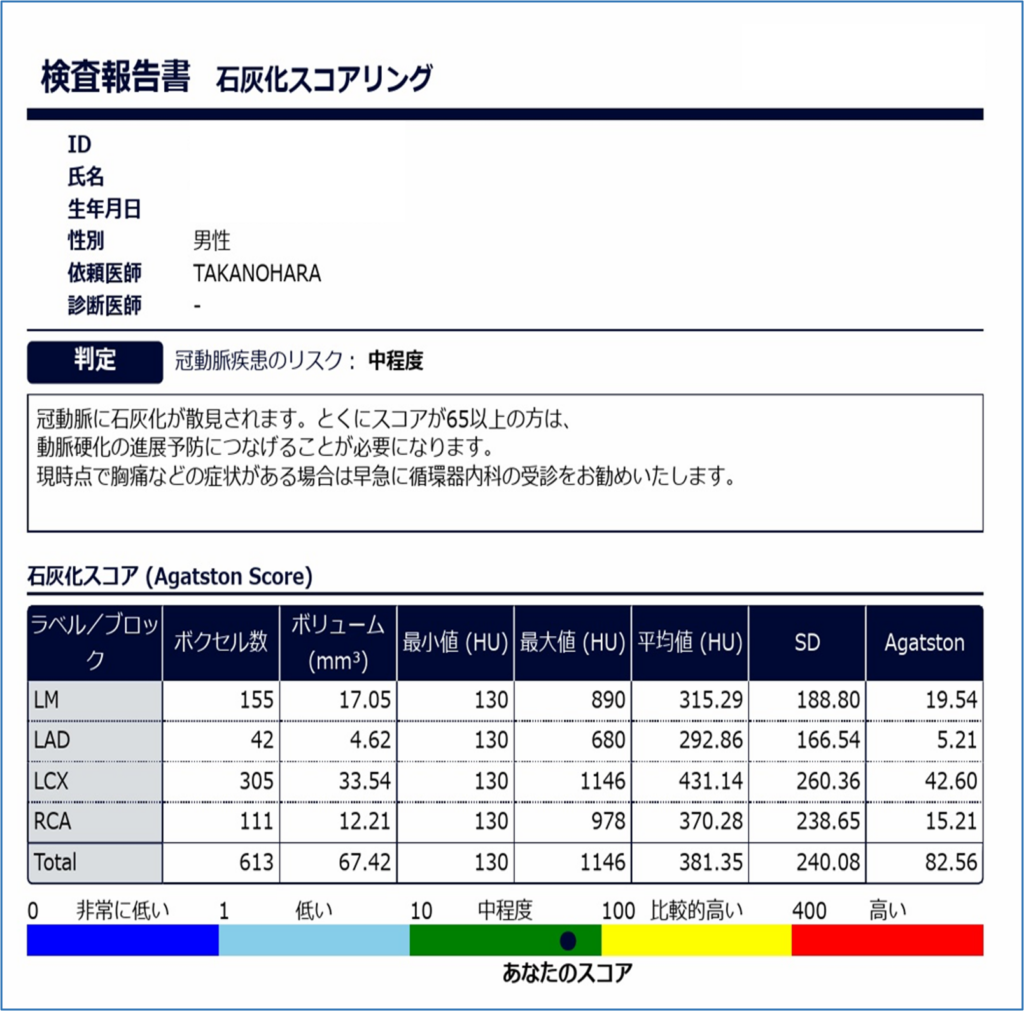

レポート形式で結果がわかる!

石灰化スコアが0である場合、冠動脈プラークや有意狭窄病変は考えにくく、リスクは極めて低いと考えられます。

冠動脈の石灰化沈着が多くなるとスコアは上昇し、100以上の場合2-5年以内の心血管イベントの可能性が高まることが分かっています。